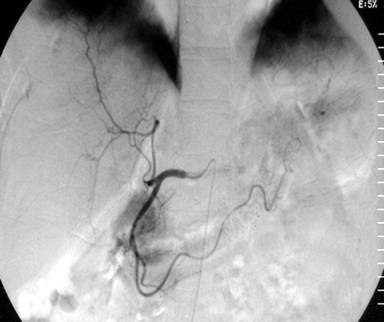

An episode of bleeding occurred two days after adrenaline injection and a repeat side view endoscopy was performed which revealed fresh bleeding from an periampullary Dieulafoy’s lesion; immediate hemostasis was achieved by the application of a hemoclip (Figure 4). After remaining asymptomatic for one week, another episode of bleeding occurred and an urgent angiography was performed. The angiogram obtained after selective catheterization of the superior mesenteric artery revealed an area of abnormal vascular blush in the second part of the duodenum arising from the gastroduodenal artery (Figure 5). As the feeder vessels were of very small caliber, super selective catheterization and embolization was not feasible. Therefore, the patient underwent surgery and oversewing of the abnormal vessel was carried out. The patient had an uneventful postoperative course and is asymptomatic with no recurrence of gastrointestinal bleeding at 18 months of follow-up.

Figure 5. Superior mesenteric angiogram: abnormal area of blush in the second part of the duodenum. |